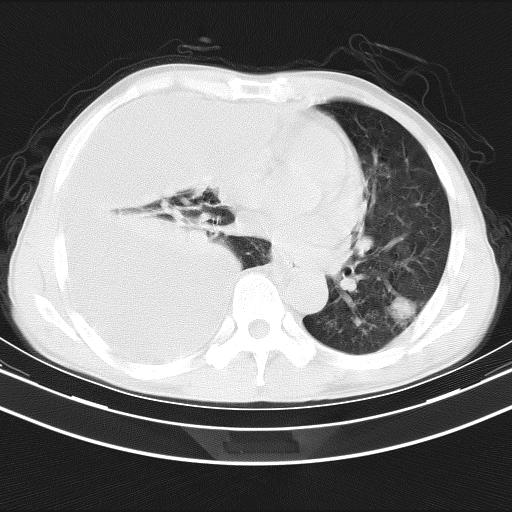

男性,44岁,结核病史多年。现胸闷气短,咳嗽,偶咳血。

右侧胸腔积液

右肺下叶不张

双肺多发结节影最分空洞形成考虑占位不除外结核

双肺陈旧性病变

1、右侧大量胸腔积液伴右肺压缩性膨胀不全,建议抽液治疗后复查 2、两肺继发性tb伴空洞形成。

1)两肺继发性肺结核伴空洞形成,左肺多发性结核球。2)右侧大量胸腔积液伴右肺部分膨胀不全。3)纵隔淋巴结肿大。